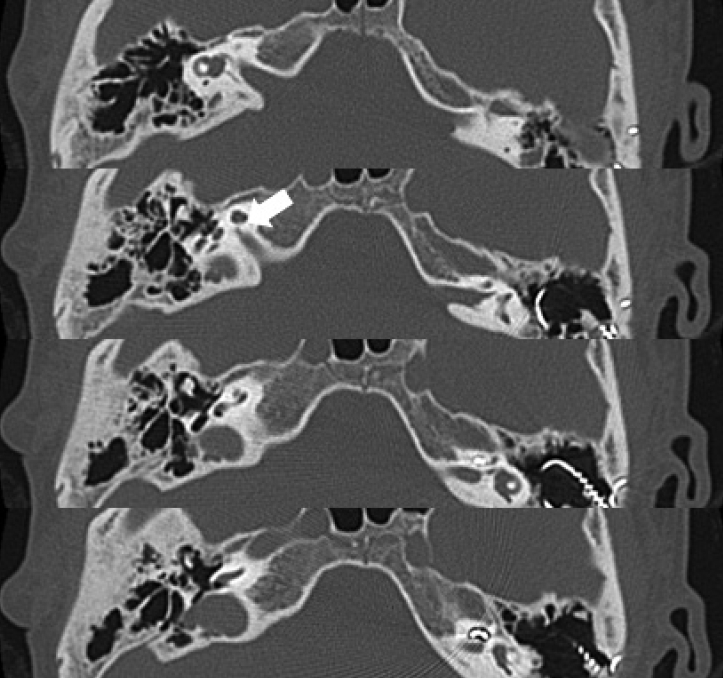

생후 20개월에 좌측 귀 인공와우이식을 받은 여아가, 13세 8개월 시점에 우측 귀의 인공와우이식을 받기 위해 내원하였다. 신체 검사에서 이전에 인공와우이식을 받은 좌측 귀의 이개, 외이도, 고막은 정상이었고, 우측 귀는 lobule type의 소이증과 외이도 폐쇄증을 가지고 있었다(Fig. 1). 순음청력검사에서 청력 역치는 양측 귀 모두 전농이었고, 좌측 귀의 인공와우 착용 청력 역치는 2 0 d B HL이었다. 좌측 인공와우착용 상태에서 시행한 말지각검사에서 단음절어 지각검사 음소점수 37%, categories of auditory performance(CAP) 점수 4였다. Receptive expressive vocabulary test에서 수용어휘가 5세 6~11개월 수준으로 또래에 비해 언어발달이 지연되어 있었다. 측두부 컴퓨터 단층촬영(temporal bone computed tomography, TBCT)에서 인공와우이식을 받은 좌측 귀는 외이와 중이가 정상이었던 반면, 우측 귀는 외이도가 뼈로 완전 폐쇄되어 있고 유양동 함기화가 양호한 Schuknecht 분류 C형의 외이도 폐쇄증을 가지고 있었다. 양측 귀 모두 동일한 형태의 와우 저형성증과 와우신경관 협착증을 가지고 있었다(Fig. 2). 12년 전 좌측 인공와우이식 수술 전 촬영한 내이도 자기공명영상[internal auditory canal(IAC) MRI]에서 양측 와우신경의 무형성증이 확인되었다(Fig. 3).

우측 인공와우이식은 외이도 성형술의 전방접근법의 술식을 적용하여 시행하였다. 정원창을 향한 충분한 시야 확보와 전극 cable이 위치할 공간을 확보하기 위해 유양동 삭개술을 최대한 넓게 시행하고 폐쇄 골판을 제거하여 malleus-incus complex를 노출하였다. 이후 정원창을 노출하기 위해 아래쪽으로 드릴링을 시행하였다. 안면신경의 고실 분절과 second genu의 골관 결손(bony canal dehiscence)이 확인되었고, 수직 분절은 급격히 전방으로 꺾어져 정원창와의 측부(lateral to round window niche)를 가로질러 주행하고 있었다. 안면신경이 정원창와를 덮고 있었으므로 석션 팁으로 안면신경을 조심스럽게 젖혀서 정원창와를 노출하고, 정원창와를 덮고 있는 골성 돌출부(bony overhang)를 드릴링하여 정원창을 노출하였다. 정원창을 절개하고 NucleusⓇ CI422 (Cochlear Ltd., Sydney, Austrailia)의 전극을 완전히 삽입한 후 골막을 이용하여 정원창을 폐쇄하였다. 전극 삽입 직후 시행한 임피던스 검사에서 모든 전극의 전기 저항은 정상이었고, 전기자극 복합활동전위 검사에서는 반응이 나타나지 않았다. 수술 후 안면신경마비는 없었고, 수술 후 3일째 퇴원하였으며 7일째 일체형 어음처리기를 착용하였다. 매핑 과정과 어음처리기 착용 동안 안면 연축은 발생하지 않았다. 수술 1년 후에 우측 귀의 인공와우 착용 청력 역치는 34 dB HL(6분법)로 개선되었고(Fig. 4), 단음절어 지각검사 음소 점수는 32%였다. CAP 점수는 grade 4로 이전과 동일하였으나, 순차적 양측 인공와우이식 후에 소리의 방향성 분별과 소음 상황에서의 의사 소통이 이전보다 나아져서 부모와 아동은 두 번째 인공와우이식을 시행한 것에 대해 만족하였다.

외이도 폐쇄증을 가진 환자가 전음성 난청이 아닌 고도 감각신경성 난청을 동반한 경우에는 인공와우이식을 시행하여야 하는데, 이 때 안면신경 주행 경로의 이상으로 인해 수술이 어려울 수 있다. 특히 본 증례와 같이 안면신경의 수직분절이 급격히 전방으로 진행하여 정원창과 와우갑각 위를 지날 경우에는, 드릴링을 통해 정원창을 노출하는 과정에서 안면신경이 손상될 위험이 있고, 전극 삽입도 어려울 수 있다. Jahrsdoerfer과 Lambert [10]은 외이도 폐쇄증으로 외이도 성형술을 시행한 1300명 중 25%에서 수술 중 안면 신경 주행 이상을 발견하였으며 이 중 11명에서 수술 중 안면신경의 손상이 있었다고 보고하였고, Chang 등[11]은 한국인 환자를 대상으로 한 연구 결과를 보고하였는데 외이도 성형술을 시행한 21명(25귀)의 외이도 폐쇄증 환자 중 4귀(16%)에서 안면신경이 전방으로 전위되어 있었다고 보고하였다. 또한 Takegoshi 등[4]은 46귀의 소이증과 20귀의 하악안면골이골증(mandibulofacial dysostosis) 환자의 TBCT를 분석한 결과, 소이증은 안면신경의 수직 분절이 정상군보다 평균 3 mm 더 전방에 위치해 있었고 하악안면골이골증 환자에서는 평균 2 mm 측방에 위치했다고 보고하였다. 외이도 폐쇄증 환자로서 malleus-incus complex의 측부를 따라 진행하는 안면신경 주행이상을 가진 증례도 보고된 바 있으므로[12] 외이도 폐쇄증 환자에게 인공와우이식을 시행할 경우에는 각별한 주의가 필요하다.